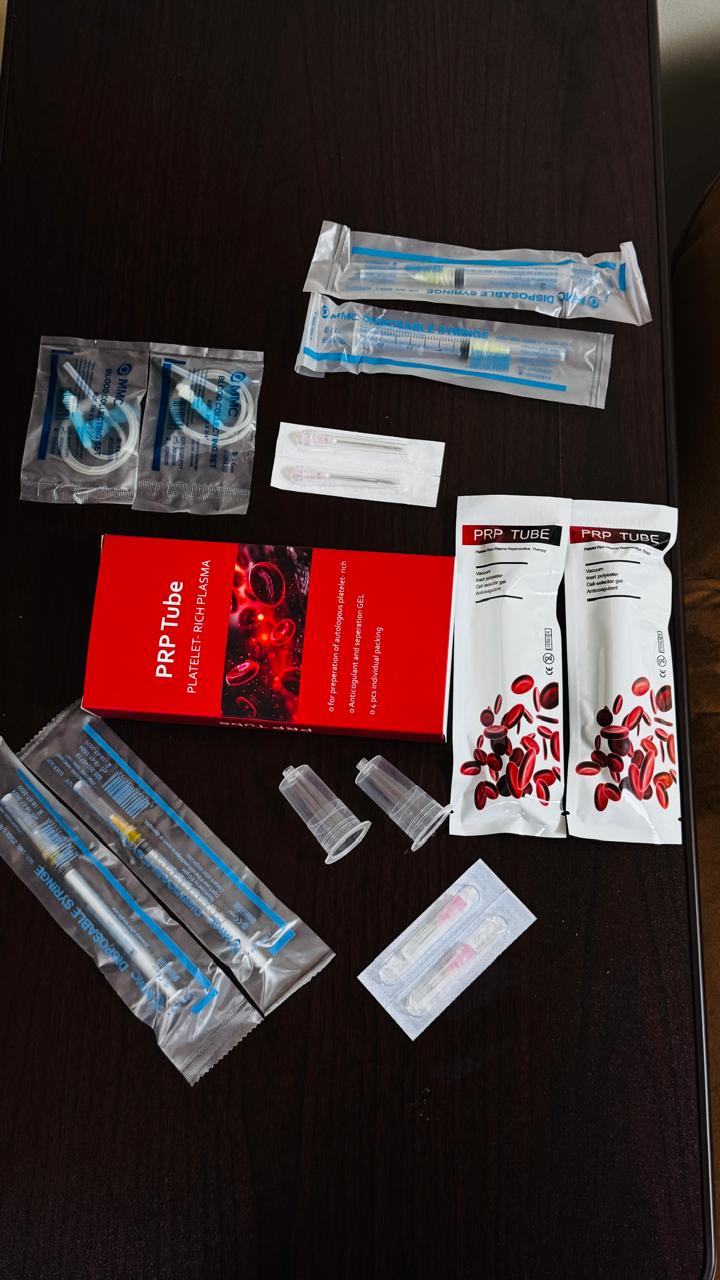

PRP KIT

PRP KIT

PRP TUBE

PRP TUBE